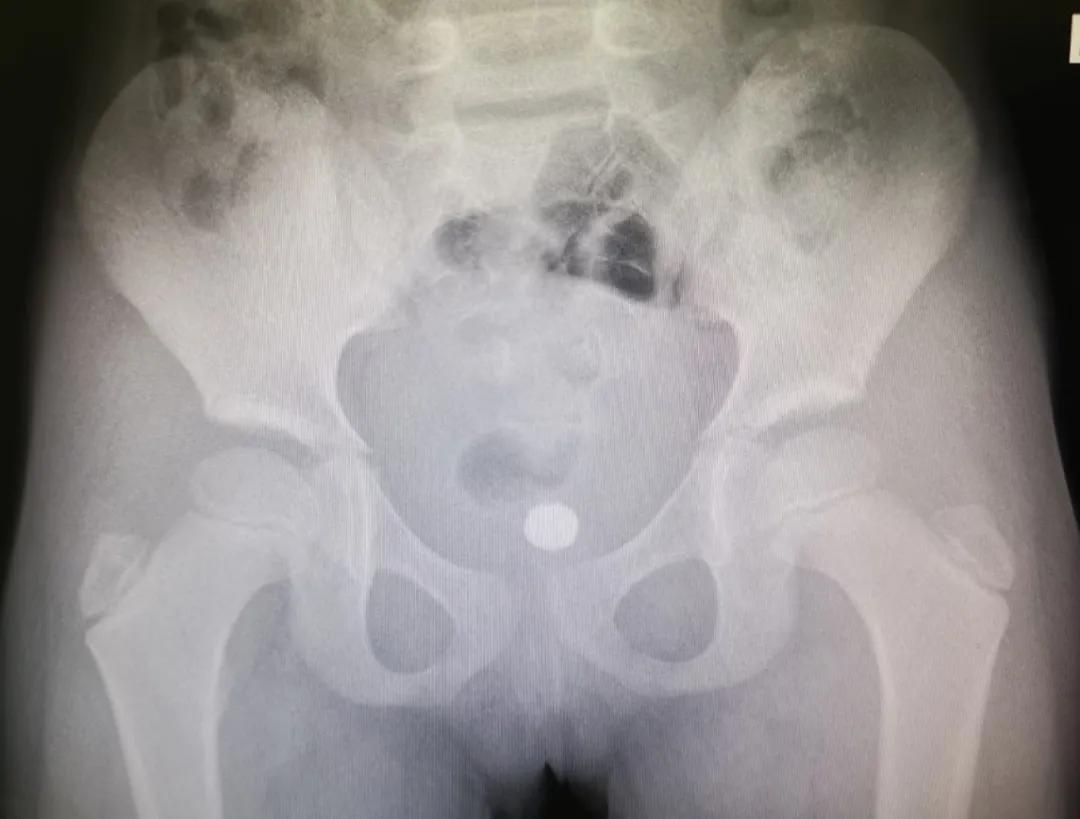

11岁男孩一个多月前,因好奇将12颗磁力珠从尿道塞入。12颗磁力珠在膀胱内紧紧相连,并吸附尿垢,形成一个中间带坚硬“结石”的较大环状异物。最终只能开放下膀胱切开取出异物。